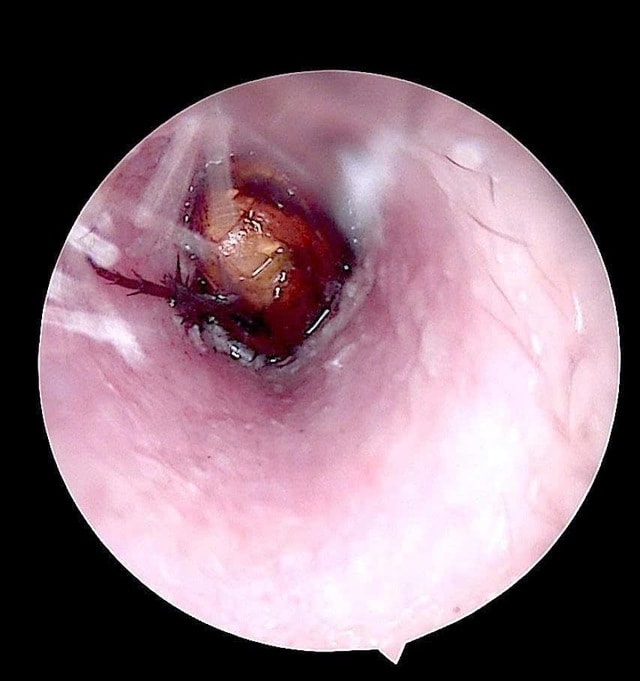

Qua kiểm tra, bác sĩ ghi nhận ống tai ngoài bên phải của bệnh nhân có hiện tượng xung huyết, có dị vật sống. Các bác sĩ đã tiến hành nội soi, gắp dị vật là một con côn trùng có kích thước khoảng 1,5cm.

Kiểm tra sau lấy dị vật, phát hiện màng nhĩ bệnh nhân nề đỏ do phản ứng viêm và kích thích trong quá trình tự lấy dị vật.